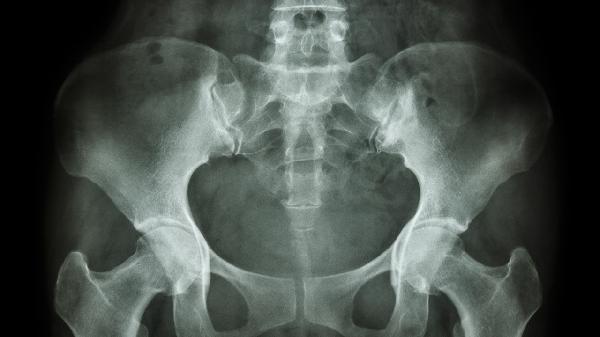

中骨盆平面狭窄的临床表现有哪些

中骨盆平面狭窄的临床表现主要有胎头下降受阻、产程延长、继发性宫缩乏力、胎头位置异常、胎儿窘迫等。中骨盆平面狭窄是指骨盆入口以下至出口以上的中段骨盆径线缩短,可能影响分娩过程。